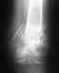

Добрый день! Двойной перелом голени. Три года назад был проведен внутрикостный интрамедуллярный остеосинтез, который надо было извлекать через пол-года после операции,

то есть просрочил уже 2 с лишним года. Вопрос - в значительной ли степени сейчас усложняется извлечение? Нога чувствует себя вполне нормально, спортом занимаюсь, но чувствуется конечно что что-то в ней есть и держать это в себе не вариант. После операции все было идеально, когда последний раз был на осмотре. Потом сказали появляться через пол-года, но я по семейным обстоятельствам не смог и только сейчас появилось время на эту операцию. Благодарю за ответы.

Именно за счет срока извлечение мало усложняется. Однако сложности могут быть обуслволены и ддругими причинами. Необходимости удаления бессимптомного фиксатора нет. Никаких непосредственных благ удаление в таких случаях не дает.